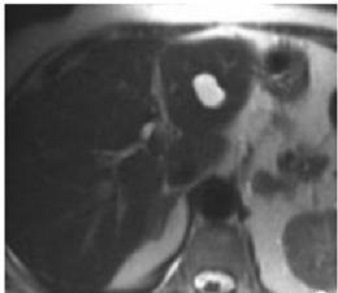

Image IRM

typique de hemangiome : Methode IRM est tres

performance de diagnostique hemagiome du foie : aspect

hyposignale en T1 et hypersignal en T2 . Cinetique de

rehaussement avec de contrast intraveineuse est resemble a

celle du TDM

Image hyposignal d'une

hemangiome du foie en coupe axiale de IRM a

travers du foie ponderee en T1 |

|

Image hypersignal

du mêm cas en coupe axiale de IRM a travers du

foie ponderee en T2 fat-sat |